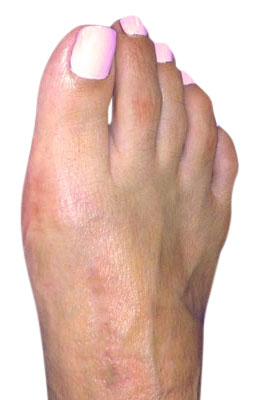

Before

Lapidus Forever Bunionectomy™ Before image

After

Lapidus Forever Bunionectomy™ after image

Lapidus Forever Bunionectomy™

Whitney, a 47-year-old businesswoman who could not fit into her dress shoes because of her bunion and terrible calluses caused by it. We performed a Lapidus Forever Bunionectomy™ on her big toes and she was able to bear weight on her foot 2 weeks after surgery and was back in her heels at 8 weeks post-surgery with no pain and now an amazing looking foot. After image was taken 12 weeks post-op.